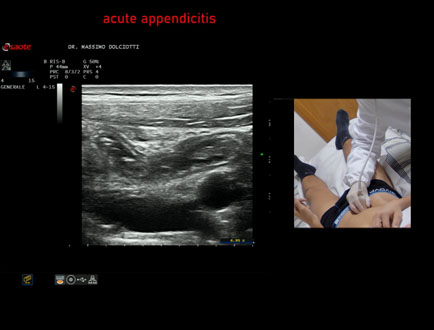

Ecografia del: 13/02/2026

Strumento: Esaote MyLab Eight

Sonda: Lineare Multifrequenza 4-15 MHz

Età Paziente: M 22 anni

Motivazione dell'esame: da un giorno dolori addominali in sede ileo-cecale.

Commento all'esame: le immagini ed il video documentano, in sede ileo-cecale, appendice di spessore aumentato (9 - 10 mm - V.N. inferiore a 6 mm) con incremento della vascolarizzazione. Gli elementi ecografici segnalati orientano per appendicite acuta.

Conclusioni: appendicite acuta (acute appendicitis).

In collaborazione: Dr.ssa Marica Manfredi - Ancona, Dr. Ilir Qose - Ancona

Presentazione: Dr. Massimo Dolciotti - Ancona

Elaborazione digitale: Andrea Dini - Ancona